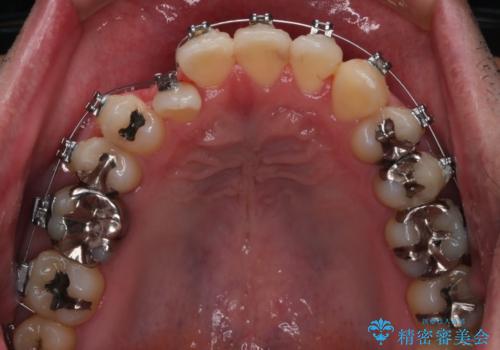

抜歯の本数を最小限に抑えたことで、治療計画も1年5ヶ月と短期間で終了することができ

主訴である前歯のがたつきも改善され綺麗な歯並びになりました。

矯正の装置を除去したタイミングで、ホワイトニングも行うことで歯の色味も白くなりました。